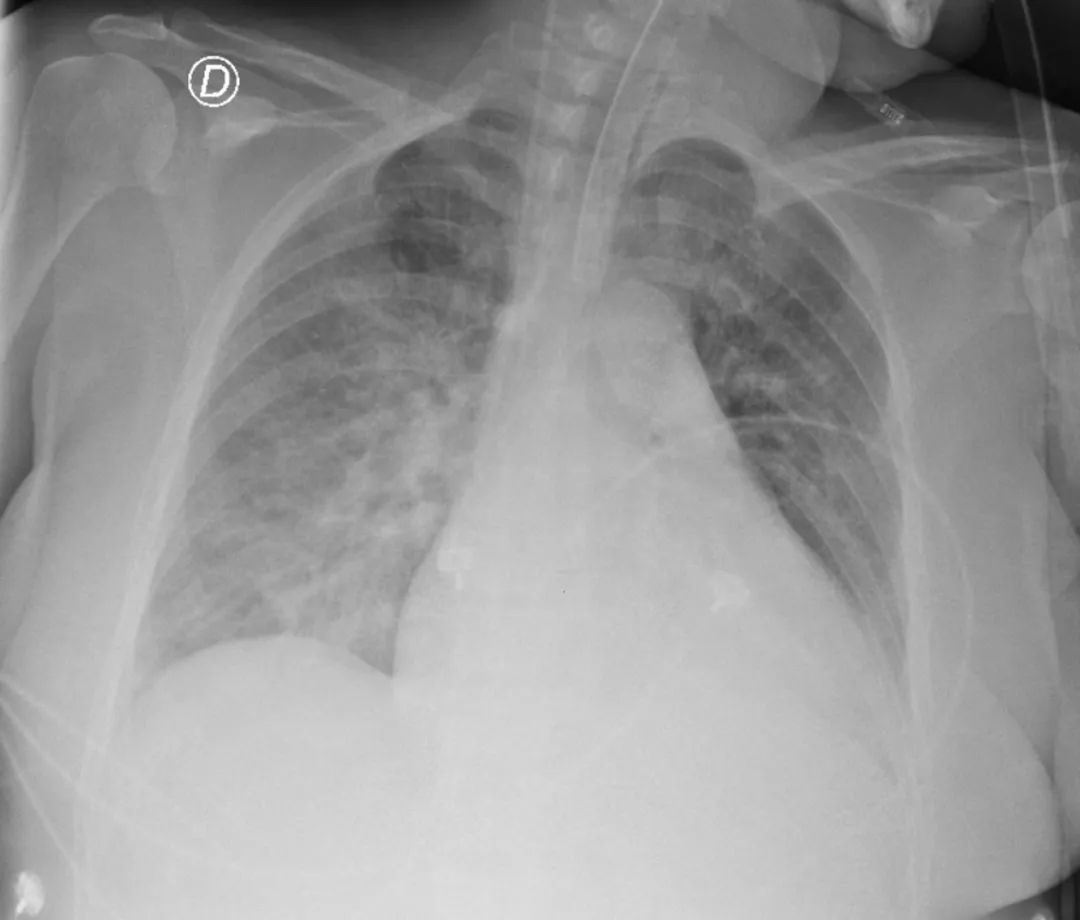

一、 病情简介患者,女性,78岁,主因“间断咳嗽咳痰3周,活动后呼吸困难5天”于2024.12.30收入笔者医院急诊科治疗。患者入院3周前着凉后出现咳嗽、咳痰,咳黄色粘痰,偶有发热,具体体温不详,自行口服感冒药后上述症状好转,遗留间断咳嗽。5天前患者出现活动后胸闷伴少量咳痰,白痰为主,夜间尚可平卧入睡,无夜间阵发性呼吸困难。1天前患者呼吸困难进一步加重,测SpO₂ 70%,就诊于我院急诊,血气分析